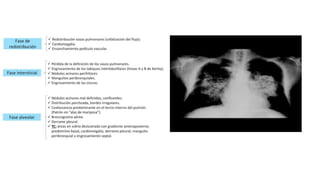

RADIOLOGÍA

2 FASES

FASE DE EDEMA INTERSTICIAL

FASE DE EDEMA ALVEOLAR

A

B

A) Se aprecia cardiomegalia y parcheado alveolar de predominio perihiliar muy característico.

B) Se señalan las líneas B de Kerley (flechas pequeñas) y el engrosamiento de la cisura menor por acumulación de líquido a dicho nivel

(flecha grande).

Se localiza principalmente en las

porciones centrales de los lóbulos

y se desvanece hacia la periferia y

es lo que se conoce como imagen

“en alas de mariposa”.

Debido al edema septal producido por

la ingurgitación de los espacios

interlobulares se producen las líneas

de Kerley

La presencia de las líneas A de Kerley (líneas

finas, largas y rectas) se visualiza a nivel de

los ápices pulmonares y son más fácilmente

visibles en la radiografía lateral.

Las líneas B de Kerley (rectas, cortas de

aproximadamente 2 cm de longitud) se

encuentran principalmente a nivel

costodiafragmático. Salvador Zubirán. Manual de terapéutica médica y procedimientos de urgencias, 6 ed. Capítulo 17: Edema pulmonar agudo cardiogénico y no